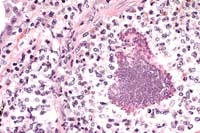

Case 27-4a. Lung. A bacterial colony and many neutrophils are plugging a small artery. and the neutrophils are transmigrating the vessel wall (bacterial embolus with necrotizing vasculitis) into the adventitia and interstitium. 40X

Case 27-4b. Lung. Foreign (plant) material plugging a bronchiole is accompanied by multinucleated giant cells. 20X

1. Multifocal, suppurative, pulmonary vasculitis and thrombosis with intralesional gram positive cocci.

2. Multifocal, granulomatous pneumonia with birefringent foreign material.

Critical features to the development of the lesions in this monkey were the jugular catheter and the epididymitis. The catheter may have injured the right atrioventricular valve, predisposing to the vegetative endocarditis and it may have also provided the source of the sepsis. Another likely source of the sepsis was the epididymitis. Injury to the endothelium is critical to the establishment of endocarditis but Staph. aureus can implant on previously "normal" valves. Bacterial emboli released from the right atrioventricular valve showered the lungs and caused an embolic pneumonia and vasculitis. A second lesion in the lungs of this monkey was the multifocal granulomatous pneumonia. This may have been the result of inhalation of foreign material during a period of illness or perhaps during one of the anesthetic procedures. Birefringent foreign material is present in the giant cells and a second type of foreign material is seen in the larger airways and is more consistent with plant or food material. Other birefringent material noted in the lungs is "mite exhaust" and acid hematin (artifact).